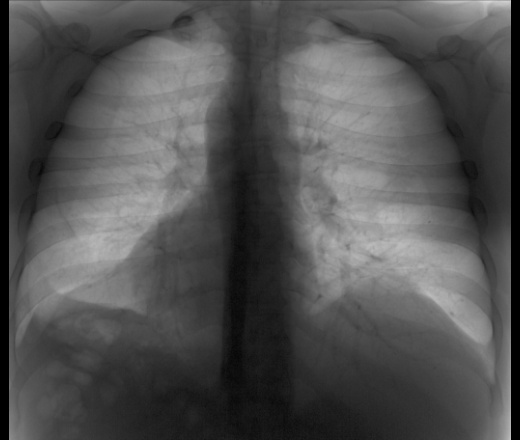

Мужчина 40 лет. Диагностическая  флюорография. Пришел на контроль, был поставлен диагноз 01.11.25 пневмония с\д, справа, в другой клинике. Смущает тень, которая видна только на задней проекции, в верхней доле справа, что это может быть? И еще, как считаете, есть выпот слева?

Справа...

Приложения:

3.jpg